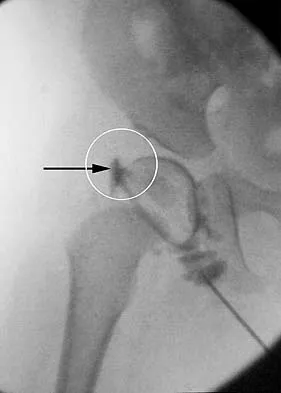

Figure 36 shows the hip arthrogram of a newborn. Which of the following structures is enclosed by the circle?

Explanation